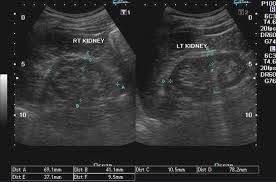

Kidney scan results your scan will go to a radiologist or other doctor trained to read the images. A gfr of 60 or higher is in the normal range. Ensure the kidney is thoroughly examined from edge to edge.

Ensure the kidney is thoroughly examined from edge to edge. We will explain everything that we see on scan and give you a clinical report of our findings and we can send them to your doctor or healthcare provider. A kidney ultrasound may be performed to assist in placement of needles used to biopsy obtain a tissue sample the kidneys to drain fluid from a cyst or abscess or to place a drainage tube. If you want to know the results of your blood tests please ask your doctor to explain them.